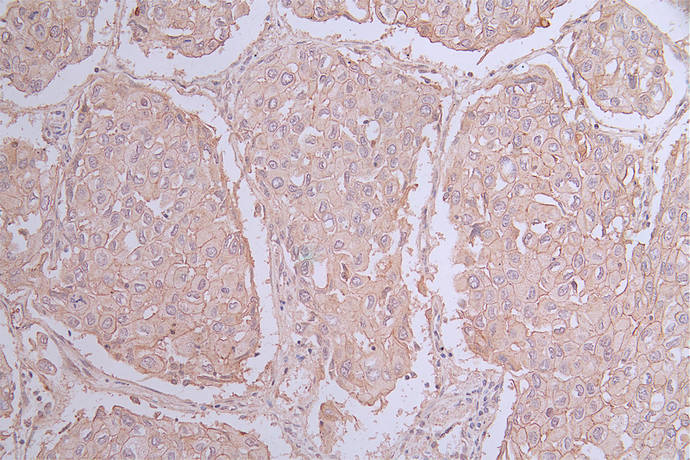

PVR(CD155)是一種細胞表面糖蛋白,屬于免疫球蛋白超家族成員,最初作為脊髓灰質炎病毒受體被發現,因此被命名為Poliovirus receptor(PVR)。PVR在多種組織和細胞類型中廣泛存在,如上皮細胞、神經細胞、免疫細胞等